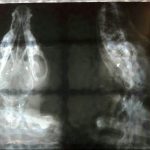

Cabe destacar que mediante los estudios practicados, «se descubrió un orificio al fondo del paladar que comunica la cavidad nasal y la boca, producto del trayecto de bala. Se retiraron esquirlas de plomo de su lengua y se evidenció también una cicatriz en ella. Los cornetes nasales están destruidos por el proyectil y las infecciones son recurrentes debido a la reacción por el cuerpo extraño y el ingreso de comida hacia la nariz. Se descartó la presencia de un tumor por lo que se pactó realizar un a cirugía reconstructiva del paladar y así cerrar el orificio», manifiesta la joven; quien aclara que se estima que se recuperará en un 90%.